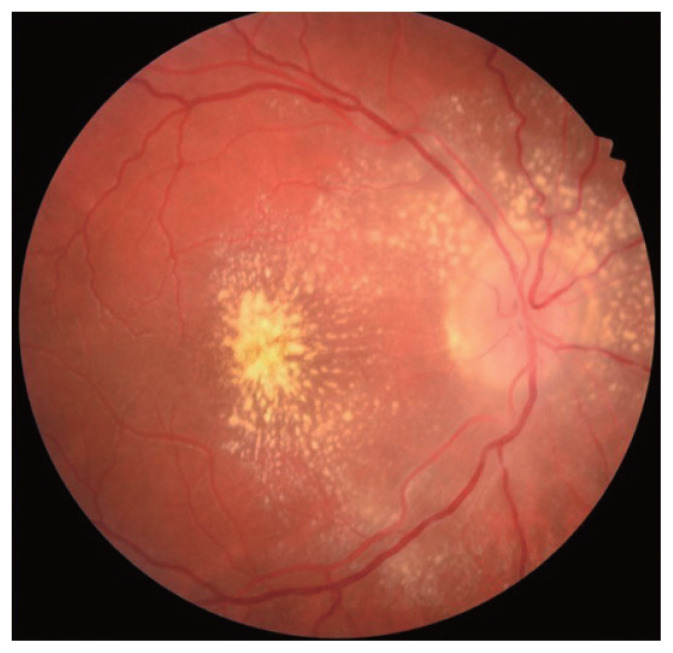

Results: Seventeen patients (19 eyes) were included with 11 (65%) being female. The mean age at presentation was 28.3 ± 12.3 years (range, 13-60 years). The mean presenting visual acuity (Early Treatment Diabetic Retinopathy Study testing) was 50 ± 23 (range, 4-90). The mean final visual acuity was 78 ± 12 (range, 45-90). Eleven patients (65%) had cats or kittens at home, with only one (6%) recounting a history of being scratched. Eight patients (47%) demonstrated the characteristic macular star at presentation, with all eventually developing macular star within a mean of 6 days. Four patients (24%) had macular oedema, three (18%) had vasculitis, two (12%) had uveitis, two (12%) had disc granuloma, and one (6%) had multifocal chorioretinitis. Six patients (35%) were treated with rifampicin and doxycycline, one (6%) with rifampicin and azithromycin, two (12%) with doxycycline only, two (12%) with co-trimoxazole monotherapy, and one patient (6%), who was breast-feeding, was treated with erythromycin. Four patients (24%) did not have receive any treatment.

Conclusions: The characteristic macular star is not always manifest at initial presentation for patients with neuroretinitis secondary to B. henselae, nor is there always a preceding history of cat exposure. Not all patients require treatment to have a good visual outcome, and the immune status of the patient is important.